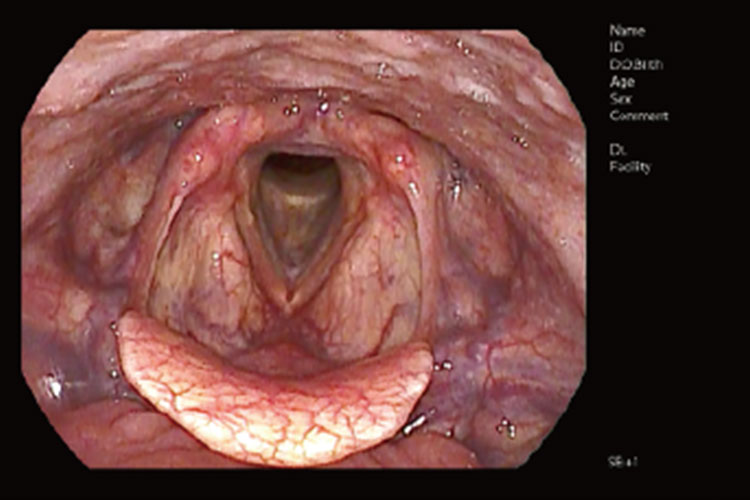

高画質内視鏡検査

内視鏡検査はクリニックレベルで概ね定着した検査機器です。

私たちは小児からお年寄りまで、自分の病気の状態を把握できるよう、患者様と一緒に「見える診療」を行ってまいります。

高画質内視鏡機器画像 内視鏡画像